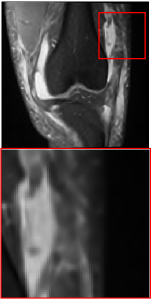

Figure 5 provides the qualitative comparison of the various methods on the four datasets at a scale of 4. The top, second, third, and bottom rows are the SR results under the FastMRI, clinical brain, clinical tumor and clinical pelvic datasets, respectively. The red boxes indicate the zoom-in region of complicated anatomical structures along with their corresponding error maps. Note that the brighter textures in the error maps, the lower the quality of the reconstructed images. As can be seen, compared to methods based on Transformers and CNNs, diffusion-based methods like DisC-Diff and DiffMSR (Ours) are capable of reconstructing high-realistic images with promising reconstruction metric scores (PSNR and SSIM). Nevertheless, while DisC-Diff can reconstruct high-precision MR images, it does not preserve the structure present in the original HR images, introducing some additional information that can affect medical diagnosis. In contrast, our method combines DM and PLWformer, which can preserve the original image’s structure while restoring high-frequency information.